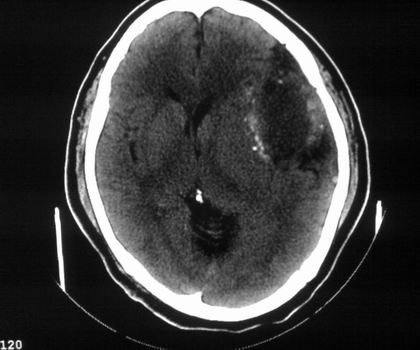

以下是引用影像孺子牛在2008-4-29 21:20:00的发言:[br]首先病变定位在脑外,根据ct密度及mri信号特征考虑慢性硬膜下血肿不连续环形钙化。

以下是引用周战梅在2008-4-29 23:12:00的发言:[br]脑外病变,蛛网膜下腔增宽,囊壁点状、环形钙化,增强扫描呈不均匀环状强化,考虑为囊性脑膜瘤可能性大,慢性脓肿、血肿机化、胆脂瘤不能除外。